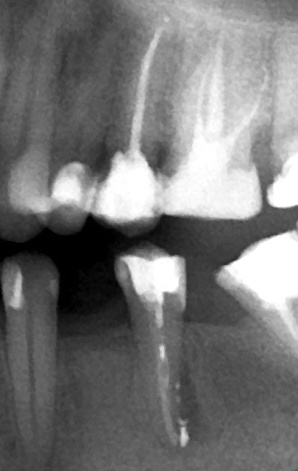

В случае ниже периодонтит развился после того, как нерв в зубе погиб. Снимок до лечения.

А это тот же зуб через 6 месяцев после лечения. Очаг на стадии заживления. Но полностью ещё не зажил. Продолжается наблюдение.

Следующий пример. Снимки слева направо и сверху вниз. До лечения, через год после лечения каналов и через 8 лет после лечения каналов. Очаг полностью зажил. Зуб не беспокоит.